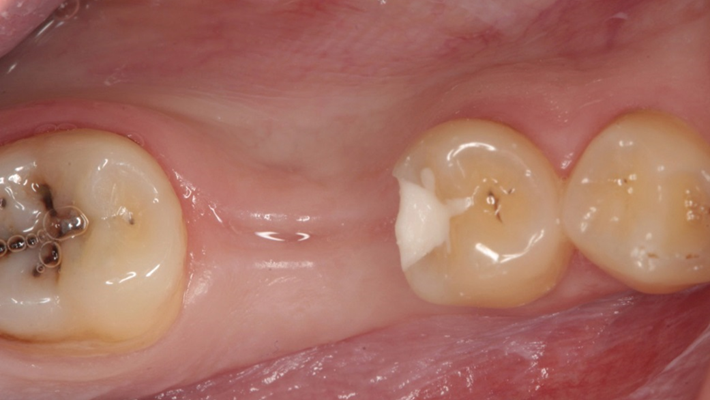

Clinical case: Delayed implant placement: sinus floor elevation by means of lateral

approach & implant placement with GBR

- Courtesy of Dr. Irfan Abas, Netherlands -